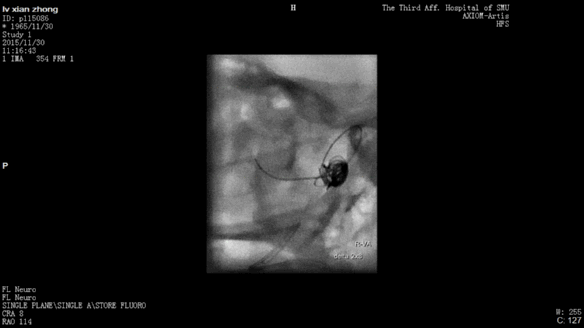

今天为大家分享的是“强生医疗CNV-神经介入专栏”第二十五期,由南方医科大学第三附属医院神经外科主任黄理金教授带来的“Enterprise支架辅助栓塞动脉瘤的优势”精彩讲课视频及PPT,欢迎观看。文章仅代表作者个人观点,如有不同见解,欢迎同道斧正!